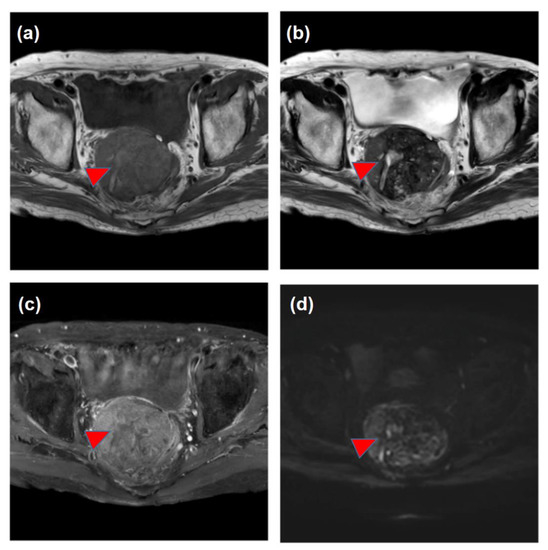

| March | Increase in the DCP and detection of the pelvic tumor Medical interview revealing mild constipation | |

| X | May | The histological diagnosis of pelvic metastasis of HCC |

| (Decrease in the tumor size and DCP values, constipation resolved) | ||